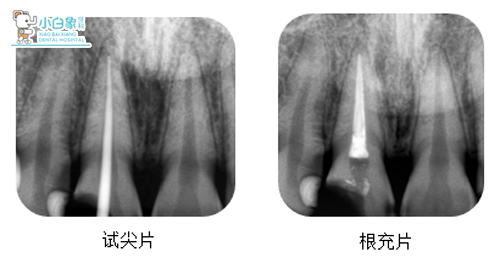

治疗过程:11必兰局麻下去腐质开髓,寻一根管,测根长22mm,M3根备至25#,超声荡洗,试尖,隔湿干燥,置牙胶尖+根管糊剂于根管内,叩(+),暂封观察。

12去腐质,隔湿干燥,纳米充填,抛光。21未处理。

十天后复诊:

检查:口内见暂封在,叩(-),温度测试无反应,牙龈无红肿。

治疗:去暂封,制备桩道,粘结纤维桩,树脂恢复牙体,制备牙体,取像,设计,研磨,试戴,上釉,粘结,戴走。